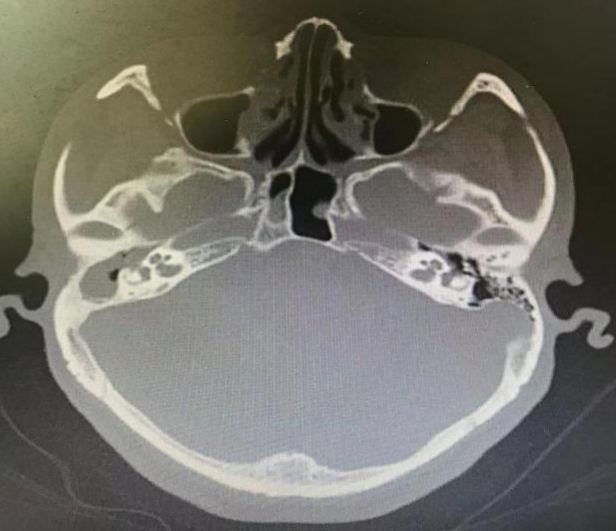

▲右侧极重度感音神经性耳聋

▲右侧外耳道后上壁破坏;右侧外半规管及面神经水平段骨质破坏

诊断:1.右侧中耳胆脂瘤。2.右侧极重度感音神经性耳聋。3.右侧周围性面神经面瘫(house 4级)。